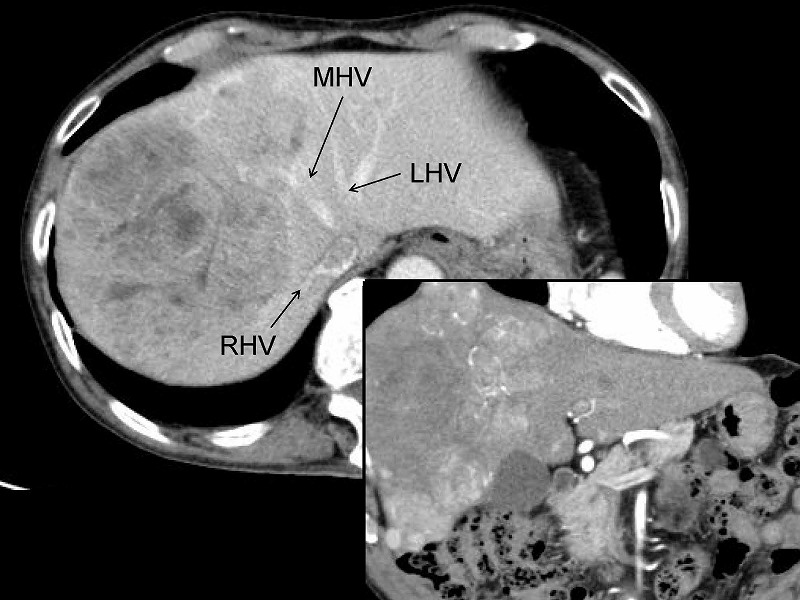

実際の症例を示しますが、肝右葉に10㎝の腫瘍を認め、中間静脈(MHV)は腫瘍にinvolveされています。右肝静脈RHVは腫瘍から少し離れて走行していました。肝予備能が良くないため、左葉と右葉後区域を温存せざるを得ません。切除に際してはCUSAと電気メスを用いて、まず左肝静脈(LHV)の内側枝に沿って切離したのち、後区域グリソン鞘G postを露出してその前面に沿って切離しました。

切除後の割面には左肝静脈LHVと後区域グリソン鞘Gpostが見えています。